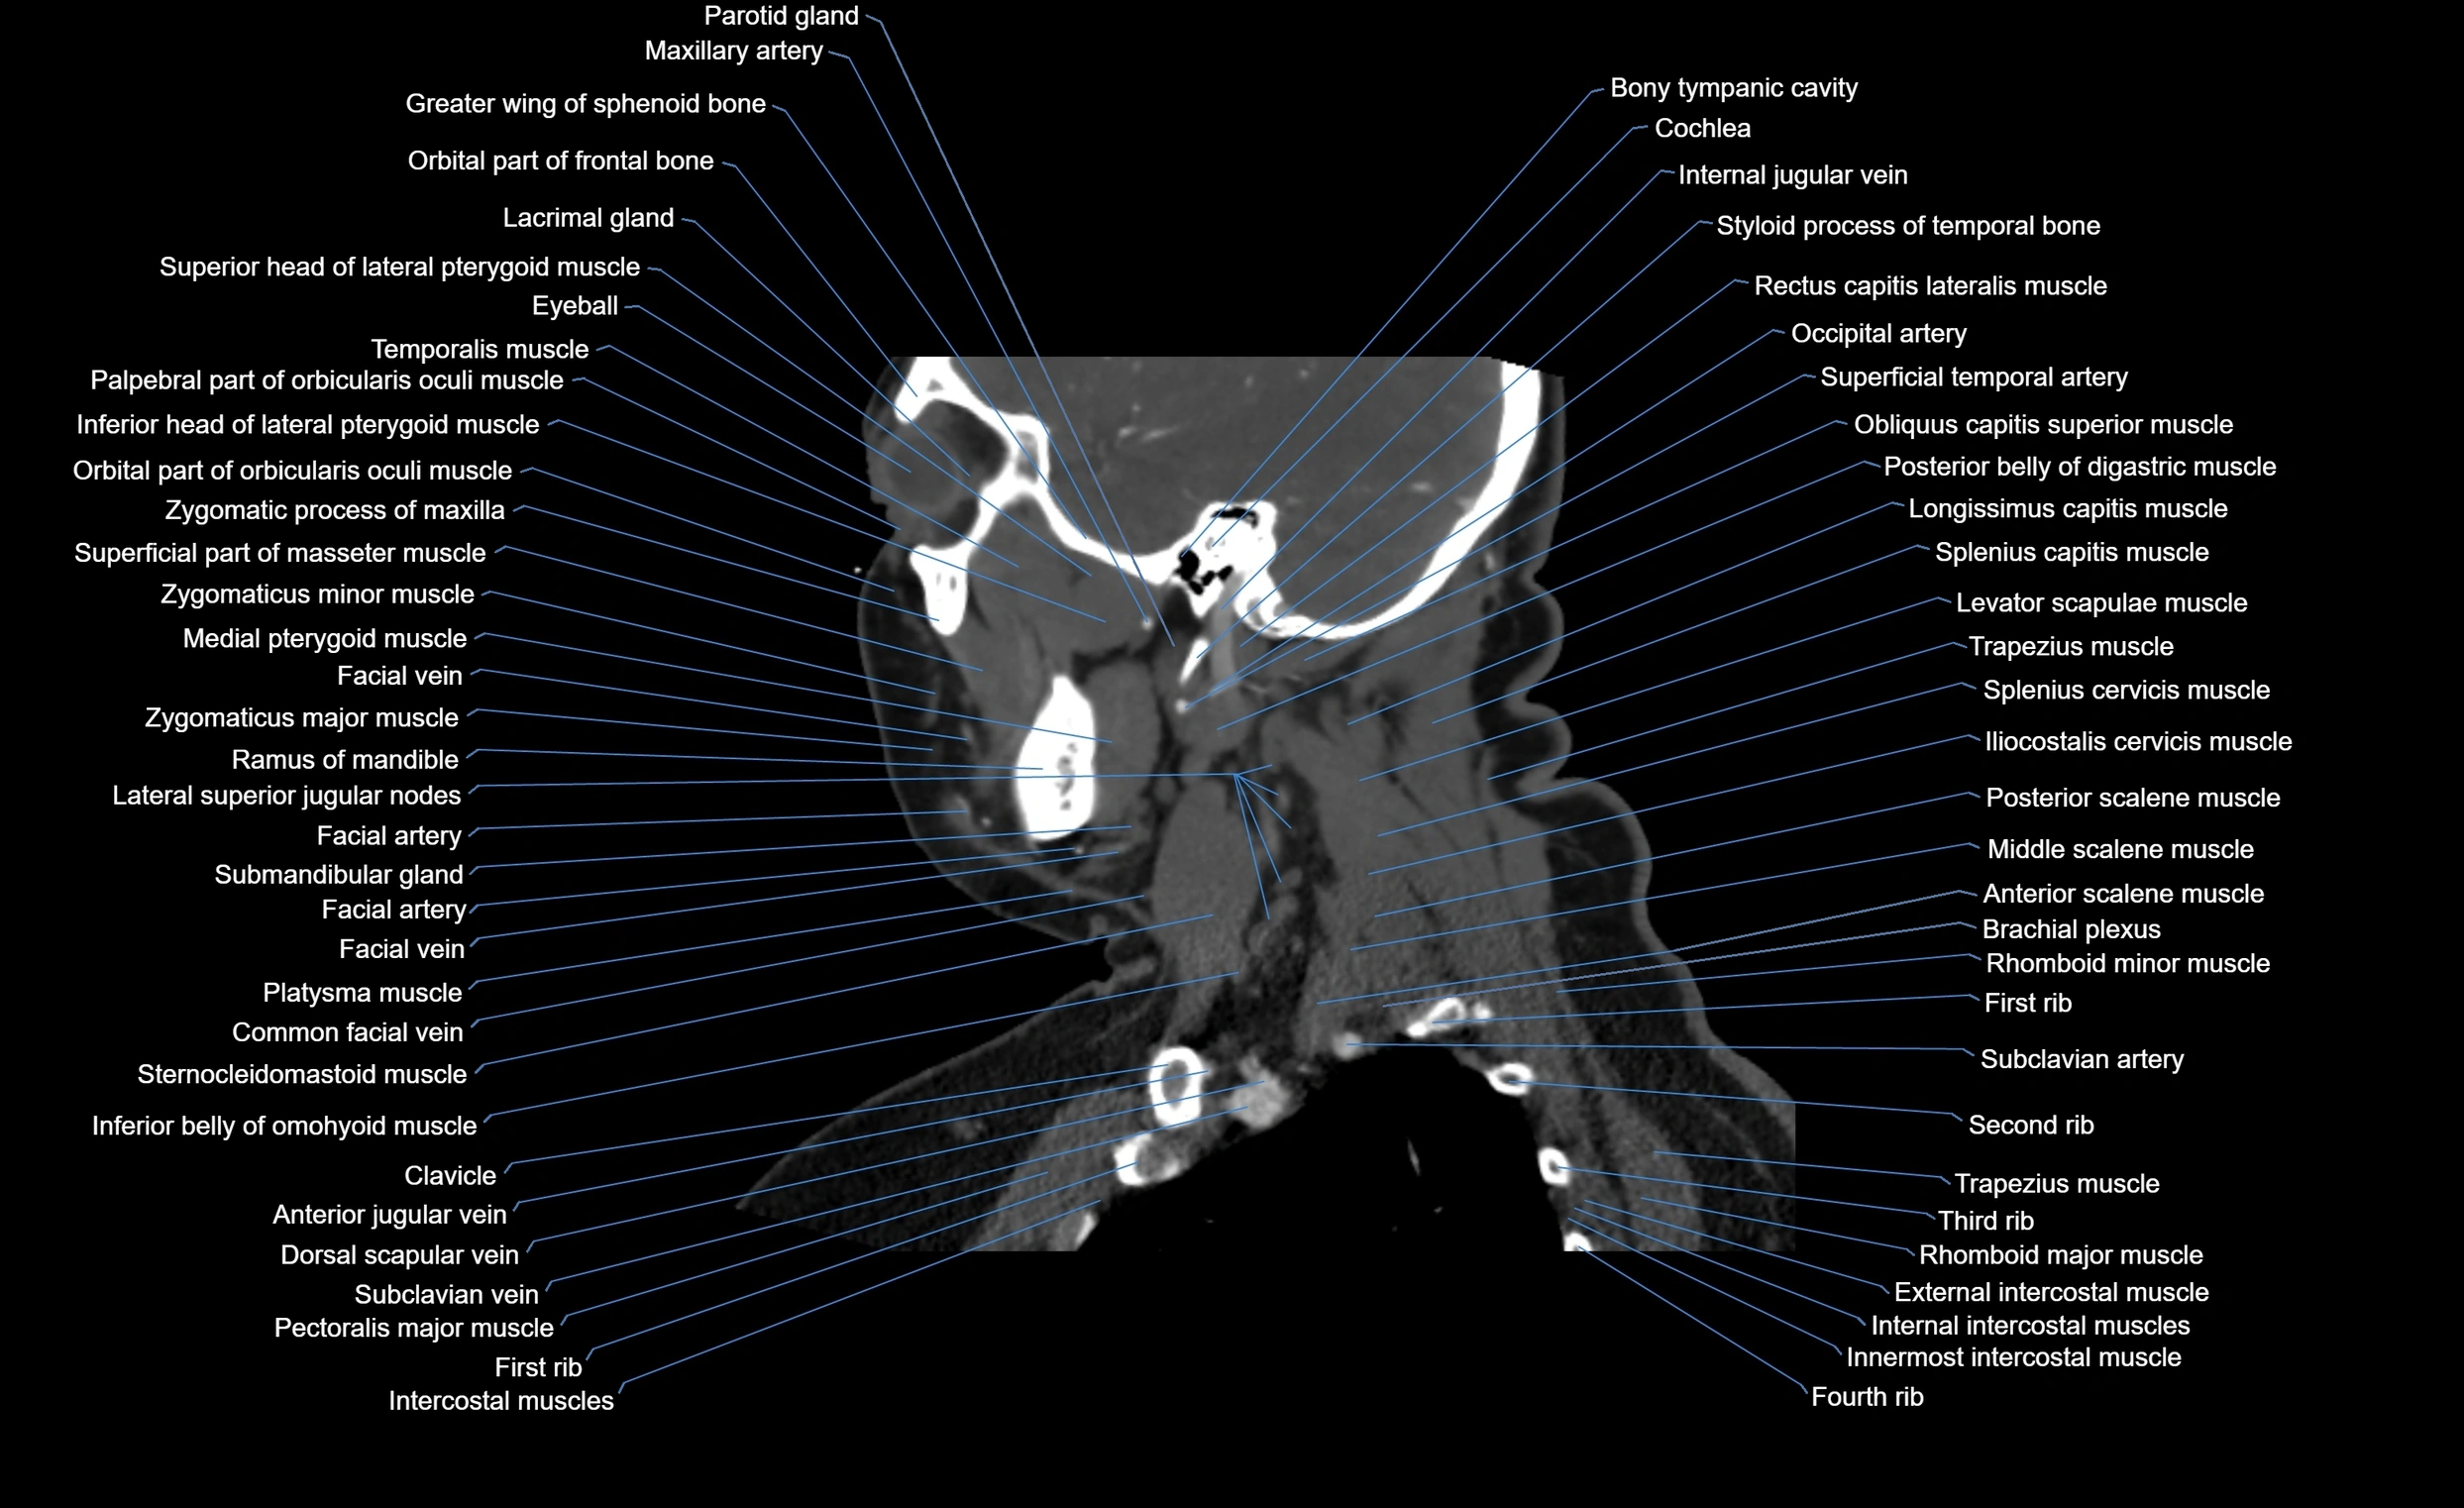

- Brachial plexus

- Clavicle

- Cochlea

- Eyeball

- Facial artery

- Facial vein

- Greater wing of sphenoid bone

- Inferior head of lateral pterygoid muscle

- Lacrimal gland

- Medial pterygoid muscle

- Parotid gland

- Platysma muscle

- Ramus of mandible

- Rhomboid minor muscle

- Rhomboid major muscle

- Serratus anterior muscle

- Sternocleidomastoid muscle

- Subclavian artery

- Submandibular gland

- Superficial temporal artery

- Trapezius muscle